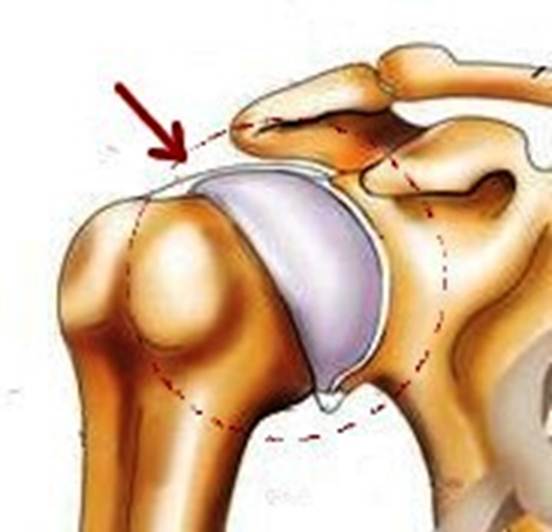

S: Стрелка указывает на art. humeri (латинский язык).

S: Стрелка указывает на lig. coracoclaviculare

S: Стрелка указывает на tendo m bicipitis brachii

S: Стрелка указывает на lig. coracoacromiale

S: Цифрой 6 обозначена суставная капсула плечевого сустава (русский язык).